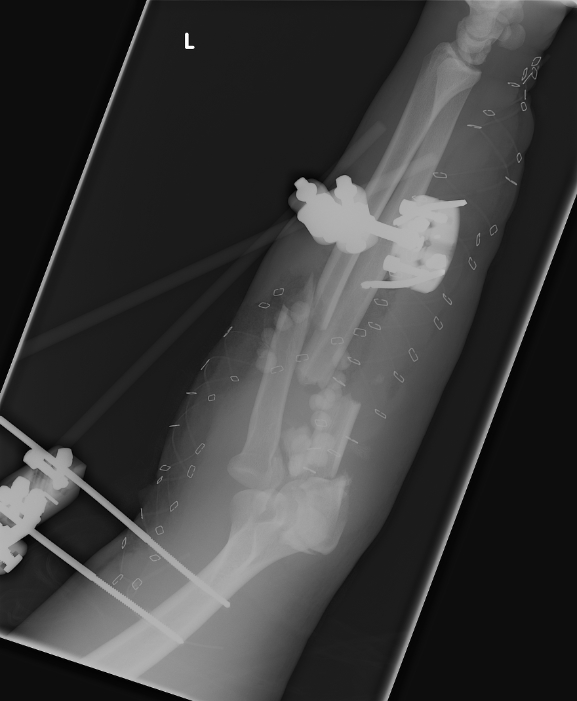

Nov 23, 2007 This picture shows both of the attachments that were used to stabilize his arm. |

Nov 23, 2007 Here you can see the broken bones in his wrist. |